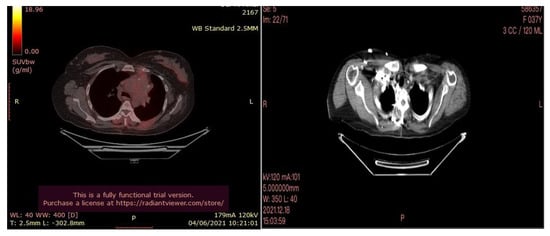

The patient, a 60-year-old man, was admitted to our Cryosurgery Unit in May 2020.

A CT scan and biopsy showed the presence of small cell lung cancer, stage IVA (T4 N3 M1a). The CT scan showed images of a hypermetabolic left pulmonary hilar tumor (Figure 3).

Figure 3. CT scan image showing hypermetabolic left pulmonary hilar tumor from male SCC patient.